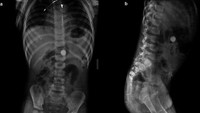

Seorang tukang kayu tidak sengaja menelan sekrup dan mengeluhkan gejala nyeri ringan perut kanan bawah. Untungnya, dokter tidak menemukan kelainan berarti sehingga sekrup itu dikeluarkan tanpa masalah. (Foto: F1000 Research)